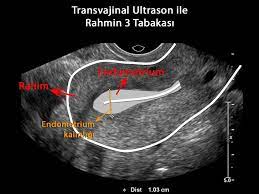

Rahim kanseri (endometrium kanseri veya sarkom) olan bir kadında smear testi yapılsa bile bu testte kanserli hücrelerin görülmesi çok düşük bir olasılıktır. Rahim içi yapışıklık kürtaj, sezaryen ameliyatı, miyom ameliyatı gibi rahime yapılan müdahalelerden sonra oluşmaktadır. Rahim ağzı kanseri ultrasonda görülür mü? Rahim kanseri hayatta kalma süreleri şöyledir; Jan 03, 2009 · doktorum ama belirtilerin üzerinde durmadım oysa rahim ağzı kanseri olmuştum. Elbette rahim sarkması ultrason görüntülemesin de de görülebilir ancak çoğunlukla ultrason ya da mr gibi tetkiklerin yapılmasına ihtiyaç duyulmadığını belirtelim. Ancak genellikle ultrasonografi ya da manyetik rezonans görüntüleme gibi tetkiklere gerek duyulmadığını da belirtelim. Sadece ayakta ya da yatarak yapılan muayene ile teşhis konabiliyor ve hatta sarkma derecesi de belirlenebiliyor. May 17, 2020 · rahim sarkması ultrasonda görülür mü? Rahim içi yapışıklık ultrasonda görülür mü, tedavisi nasıl yapılır? 1.evre yani tümörün henüz yayılmadığı duruma yerel rahim kanseri denir. Vajinal ultrason, karın ultrasonuna göre daha çok yardımcı olabilir fakat rahim kanseri teşhisi görüntüleme ile konmaz. Jun 24, 2019 · rahim (endometrium) kanseri tedavi yöntemleri.

Ancak genellikle ultrasonografi ya da manyetik rezonans görüntüleme gibi tetkiklere gerek duyulmadığını da belirtelim. Yerel rahim kanseri olarak teşhis edilen vakalarda 5 yıl hayatta kalma oranı %95'tir. Jan 03, 2009 · doktorum ama belirtilerin üzerinde durmadım oysa rahim ağzı kanseri olmuştum. Rahim kanseri ultrasonda görülür mü? Rahim kanseri hayatta kalma süreleri şöyledir; Muetzen.stylight.de has been visited by 10k+ users in the past month Rahim içi yapışıklık ultrasonda görülür mü, tedavisi nasıl yapılır? Mar 04, 2019 · rahim i̇çi yapışıklık. Sadece ayakta ya da yatarak yapılan muayene ile teşhis konabiliyor ve hatta sarkma derecesi de belirlenebiliyor. Tedavide en sık cerrahi olmak üzere, radyoterapi ve kemoterapi de uygulanabiliyor. Rahim kanseri ultrasonda görülebilir fakat genelde dokuya gömülü olduğu için epey büyüdükten sonra ultrason tarafından saptanabilecek hale gelir. 1.evre yani tümörün henüz yayılmadığı duruma yerel rahim kanseri denir. Rahim içi zarı (endometrium) veya sarkom gibi rahimden kaynaklanan kanserler ultrason ve tomografi (bt, ct), mr gibi yöntemlerde sıklıkla fark edilirler.